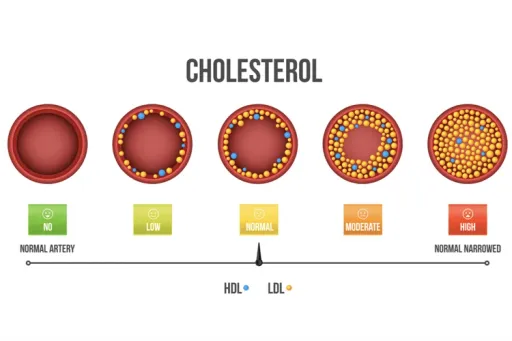

Statin